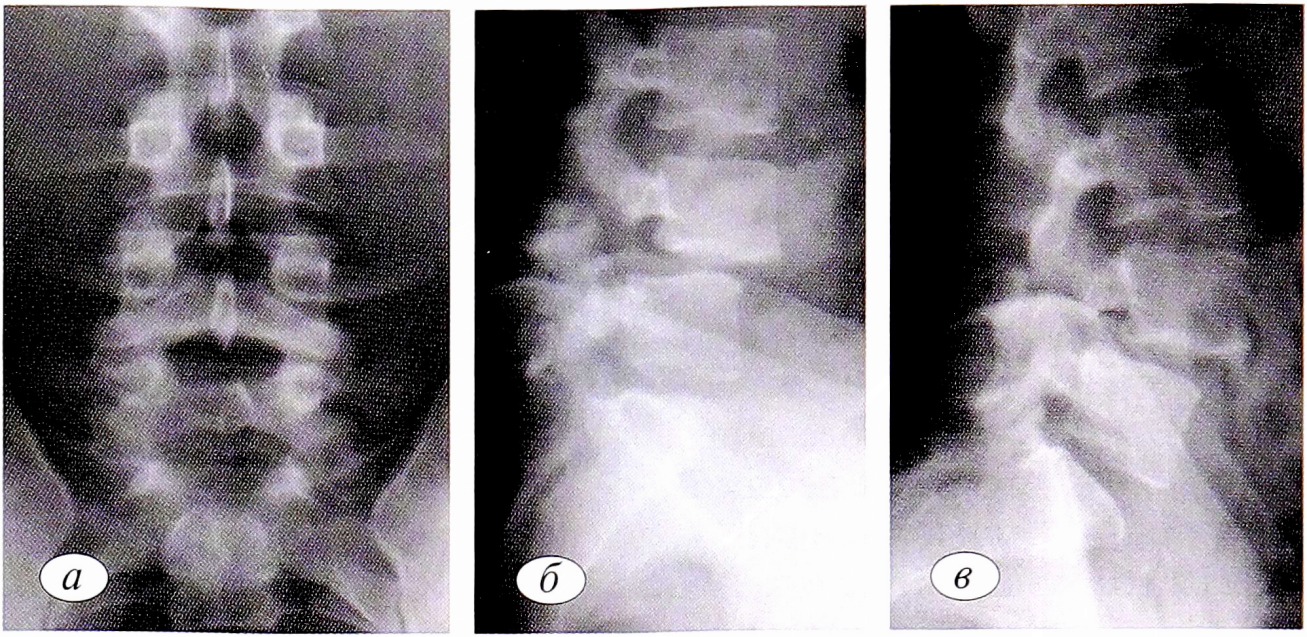

На рентгенограммах поясничного отдела позвоночника в прямой проекции линия спондилолиза, проходящая под основанием или через овал контура ножки дуги, обнаружена только у 42 (19,8%) пациентов. В этих случаях имелось совпадение плоскости дефекта с ходом центрального луча. У спортсменов и артистов балета встречались дефекты и в области перешейка дуги, и в заднем отделе дуги, в основном позвонка Lv (рис. 1).

Рис. 1. Пациентка Г.,19 лет, артистка цирка, пластическая акробатка (а). Рентгенограммы поясничного отдела позвоночника: б — прямая проекция — спондилолиз Lv, оссификаты в области дефекта дужки в результате нестабильности; в — боковая проекция — спондилолиз перешейка дуги Lv, нестабильность Lv-SI.

Fig. 1. Patient G.,19 years old, circus performer, plastic acrobat (a). Radiographs of the lumbar spine: b — direct projection-Lv spondylolysis, ossifications in the area of the arch defect as a result of instability; c — lateral projection — Lv arch isthmus spondylolysis, Lv — SI instability.

На рентгенограмме поясничного отдела позвоночника в прямой проекции у 93 (43,8%) пациентов обнаружены также варианты развития в переходной пояснично-крестцовой зоне. Это spina bifida, аномалия тропизма межпозвонковых суставов, высокий крестец.

На рентгенограмме поясничного отдела позвоночника в боковой проекции основным симптомом спондилолиза также является дефект дуги позвонка. Он был обнаружен в 169 (84,6%) наблюдениях.

При функциональном обследовании спондилолиз становится отчетливо видимым; он был диагностирован у 205 (96,7%) пациентов.

Смещение тела позвонка кпереди более чем на 2 мм, расцениваемое как антелистез, обнаружено у 41 пациента. Нестабильность в позвоночном двигательном сегменте выявлена в 197 случаях. Это выражалось в изменении формы межпозвонкового промежутка по сравнению с соседними сегментами и смещении тела позвонка при функциональных пробах (рис. 2).

Рис. 2. Рентгенограмма (а) и функциональные рентгенограммы (б, в) поясничного отдела позвоночника больного К.,25 лет (мастер спота международного класса, греко-римская борьба, сборная России). а — двусторонний спондилолиз LIV; б, в — спондилолизный спондилолистез LIV, нестабильность.

Fig. 2. Roentgenogram (a) and functional roentgenograms (b, c) of the lumbar department of the bell - ringer of the patient K.,25 years old (master spot of the international class, Greco-Roman wrestling, Russian national team). a — bilateral spondylolysis LIV; b,c — spondylolysis spondylolisthesis LIV, instability.